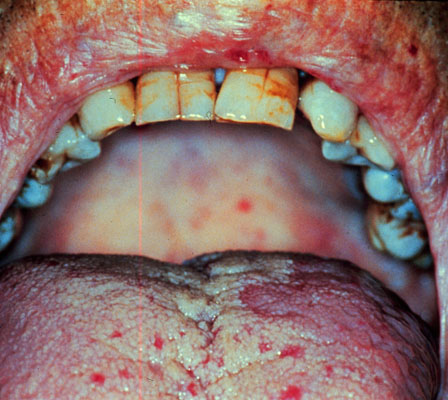

Idiopathic thrombocytopenia purpura, petechiae

A person with idiopathic (immune) thrombocytopenia purpura has petechia on the tongue and palate. Petechiae are small pin-point hemorrhages of small capillaries in the skin or mucosa, and are seen primarily in defects of platelet plug formation.